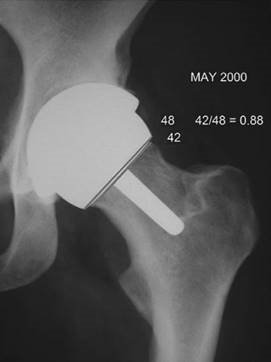

Reprinted from Journal of Arthroplasty, 23, 8, Spencer, S., Carter, R., Murray, H., and Meek, R.M., 'Femoral neck narrowing after metal-on-metal hip resurfacing', pp. 1105–1109, Copyright 2008, with permission from Elsevier..

What type of bearing is this?

This is a hip resurfacing arthroplasty, with a large-diameter, cobalt–chrome, metal-on-metal bearing.

What are its advantages over a conventional bearing surface?

1. Low wear: after an initial period of bedding-in wear, these devices have a linear wear rate of less than 0.01 mm/year, compared with metal on UHMWPE bearings which have a linear wear rate of

0.1–0.2 mm/year

2. Hydrodynamic lubrication: hip simulator studies suggest that a large-head metal-on-metal articula-tion is capable of fluid-film lubrication. It is likely that boundary lubrication occurs when the hip is at rest and a fluid film only when the hip is moving

What factors infl uence the type of lubrication achieved?

1 . Radial clearance: this is the gap between the acetabular and femoral bearing surfaces. A large radial clearance results in polar bearing and boundary lubrication. A small radial clearance may result in equatorial bearing. There is therefore an optimal radial clearance for each size of femoral component, which is small enough to allow fluid-film lubrication but large enough to prevent excessive wear and cold-welding

2. Femoral head diameter: large femoral heads are more likely to induce fluid-film lubrication

3. Component position: a high cup abduction angle can increase the risk of edge loading which in turn results in boundary lubrication

Are there any adverse eff ects with this type of bearing?

1. Cancer risk: metal-on-metal articulations produces large numbers of very small wear particles. In addition, high levels of cobalt and chrome are measured in the blood of patients with this type of bearing surface. There is concern, although no definitive evidence, that this may increase the risk of developing some types of cancer

2. Inflammatory masses: some patients with metal-on-metal hip resurfacing arthroplasty have devel-oped large, local inflammatory masses caused by metal wear debris